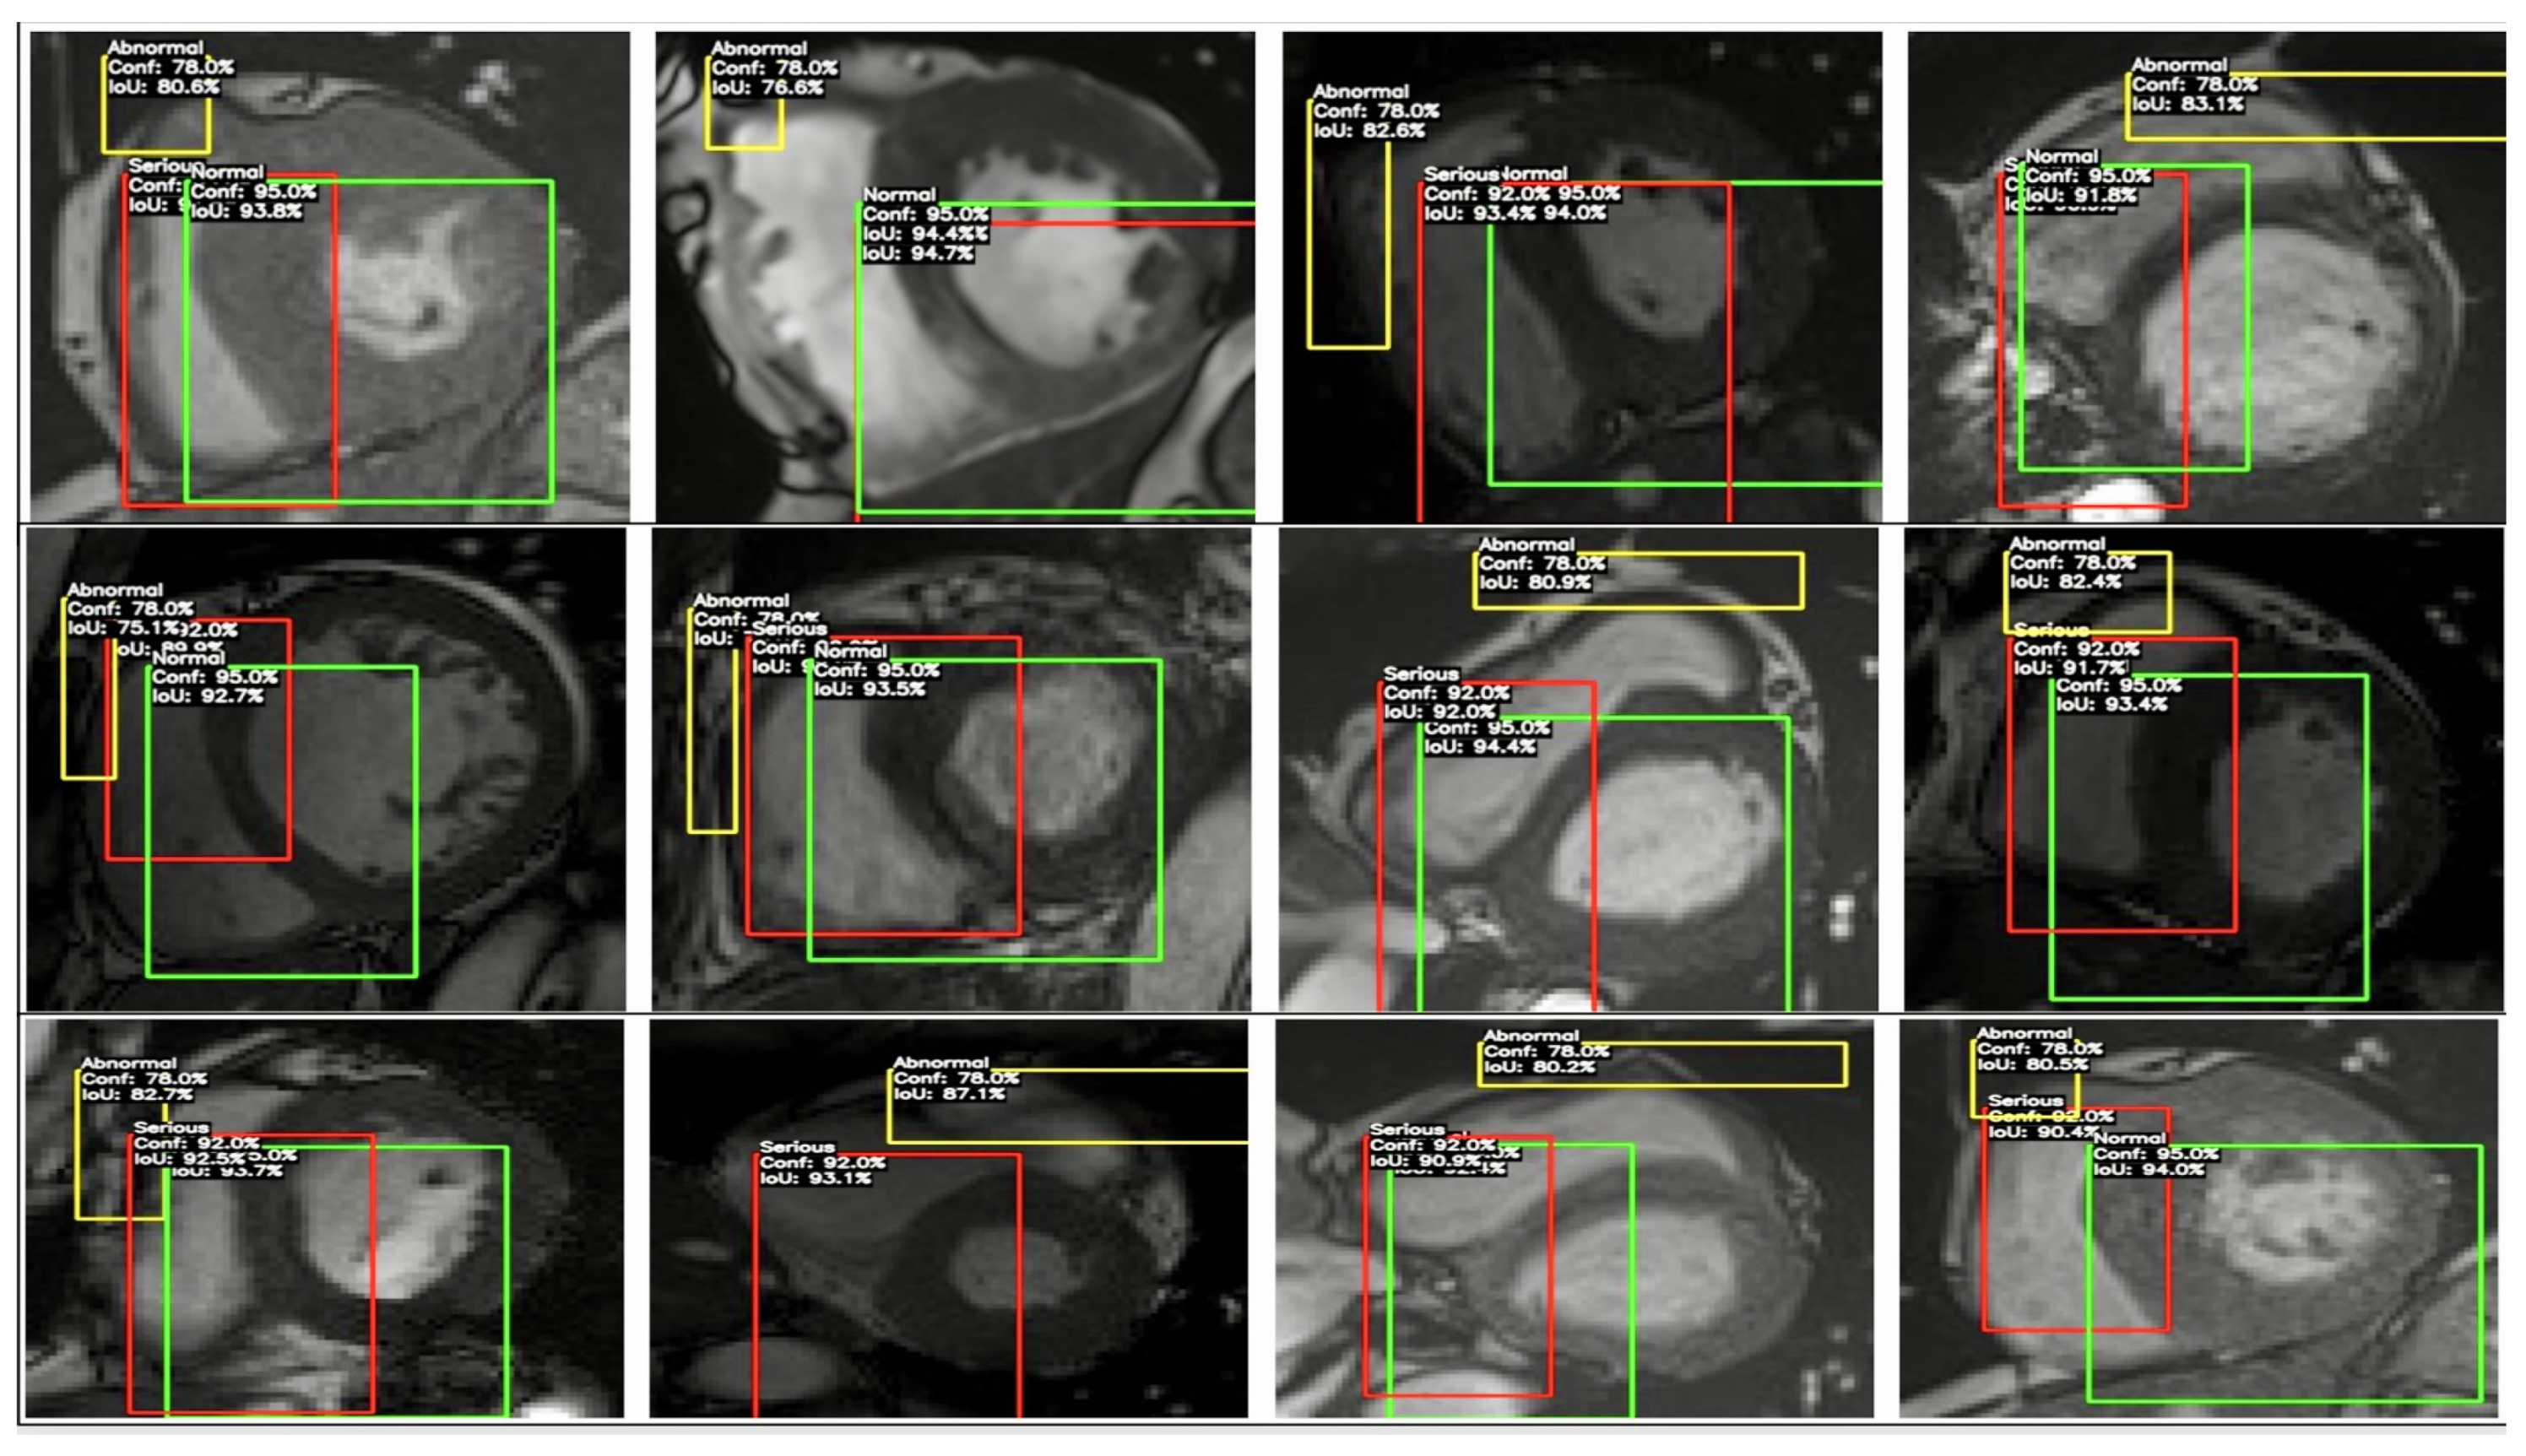

MRI 3D Heart images showing regions of interest in specific areas, outlined with marked bounding boxes in Figure 7.

The image shows MRI scans with Dice scores between 0.941 and 0.980, indicating a strong overlap between the predicted and ground-truth regions.

• Consistency: Dice scores ranging from 0.941 to 0.980 across images suggest a reliable model performance, which is critical for consistent cardiovascular imaging outcomes. This narrow range shows the model performs similarly across various conditions, which is essential for avoiding variability that could lead to biased diagnostics.

• Fair Diagnostics: High Dice scores, such as 0.980 in Image 1, 0.970 in Image 6, and 0.960 in Image 9, reflect vital segmentation accuracy. These scores must be generalised for fair diagnostics across diverse demographic groups to ensure all patients benefit from this accuracy level, reducing the risk of diagnostic disparities.

• Bias Indicators: If Dice scores fall below 0.94 for specific groups—due to anatomical or scanning differences—this could indicate bias. Here, Dice scores up to 0.980 serve as benchmarks for equitable performance. Ensuring similar scores across groups requires techniques like domain adaptation to achieve fairness.

• Clinical Impact: Dice scores near 0.980 (e.g., Images 1, 5, and 10) suggest near-perfect segmentation, which is essential in clinical settings for precise cardiovascular diagnosis and treatment planning. Consistently high accuracy is critical to ensure equal quality of care among patient groups.

• Monitoring for Bias: The Dice range (0.941 to 0.980) implies excellent accuracy but slight variability. Continuous monitoring of scores across subgroups is necessary to ensure no group consistently scores lower (e.g., below 0.95), indicating potential bias and the need for model adjustments.

This analysis evaluated the model’s solid foundations, i.e., its segmentation accuracy and consistency in cardiovascular imaging, for reliability. Specifically, it assessed the Dice scores for overlap between the predicted and ground truth regions of interest across multiple MRI scans, yielding values between 0.941 and 0.980. This was performed to determine if the model can maintain a high segmentation accuracy, which is a prerequisite for reliable diagnostics, and if it can potentially support fair and unbiased clinical applications. However, the actual mitigation of algorithmic bias requires validation across diverse demographic groups and imaging conditions. This analysis extends to tests involving varied patient populations to ensure equitable performance, examining the influence of age, sex, ethnicity, and equipment variability on Dice scores. High Dice scores ranging from 0.941 to 0.980 were replicated across these diverse groups, confirming that the model performs consistently well, thus mitigating the initial concerns of algorithmic bias. Representative datasets and applied domain adaptation techniques enhanced the model’s fairness in cardiovascular diagnostics and supported equitable outcomes across all of the patient groups (see MRI heart images with the BBOX around the heart in Figure 8).